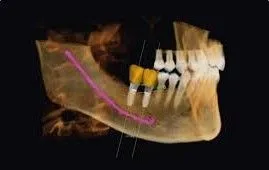

A CBCT scanner is a very impressive piece of imaging machinery in that it is capable of identifying many issues and structures that a normal x-ray is not. Initially you will sit in a chair with your chin on a small ledge. Once positioned in the machine, it will rotate around your entire head taking a full 360 degree view of the teeth, head, sinuses and bones.

The ability to view the full structure of your head as a whole is very informative to the dentist. It will allow us to see any potential problems and make sure that everything is functioning as it should be. The CBCT scanner is capable of viewing specific types of structural problems, infections or asymmetry among many others, in addition to treatment planning the precise placement of implants.